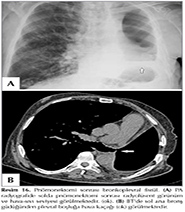

Plevra yaprakları arasındaki yapışıklıklar nedeniyle plevral boşluktaki sıvı yer değiştirmediği i?in tabanı plevraya yerleşmiş kitleye benzer bulgu verebilir (ankiste-lok?le plevral sıvı). Bu g?r?n?m ampiyem, hemotoraks veya t?berk?loz pl?rezi gibi yoğun plevral infilamasyonlarda g?r?lmektedir (1,4,5,7). Lok?le plevral sıvı lateral dek?bit radyografide yer değiştirmez. Ultrasonografi ve BT bu tip patolojilerde daha yararlı olmaktadır (5,7). Konjestif kalp yetmezliğinde sıklıkla interlober fiss?rde sıvı toplanmaktadır. Min?r veya maj?r fiss?rde toplanan sıvı konveks konturlu, oval veya yuvarlak sınırları muntazam opasite şeklinde g?r?lmektedir (Resim 3). Bu bulguya fantom t?m?r-yalancı t?m?r bulgusu (vanishing t?m?r) adı verilmektedir (7,11,12).

Resim 3